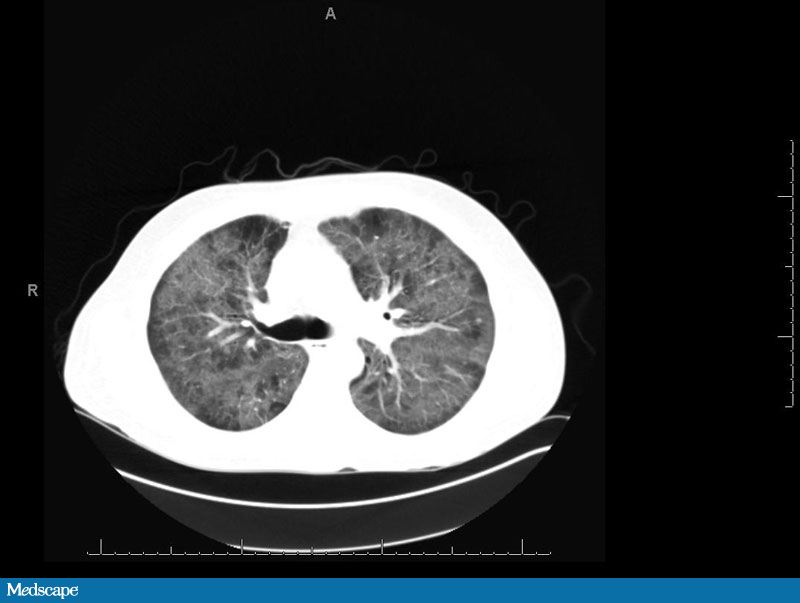

O eletrocardiograma apresenta taquicardia sinusal. A gasometreia do sangue arterial do paciente é compatível com alcalose respiratória crônica. A radiografia de tórax mostra aumento de marcações inetrsticiais difusa e bilateral e angiotomografia computadorizada (TC) de tórax demonstra opacidades difusas em vidro fosco, sem linfadenopatias ou embolia pulmonar (Figuras 1 e 2). A contagem de glóbulos brancos é de 5,2 × 103/μL. A contagem de linfócitos CD4 é de 38 células /μL. O resultado quantitativo sobre HIV-1 RNA PCR é 1.710.000 cópias / mL. Rotina de sangue e as culturas de urina são negativos. Uma amostra de escarro induzido é enviada para análise.

O estudo de imagem inicial adequada para os pacientes imunocomprometidos com sintomas pulmonares ou constitucional é o Raio-X tórax. Radiograficamente, o PCP clássico apresenta-se como infiltrado intersticial bilateral perihilar que se torna mais extensa e pode progredir para consolidações em vários dias. Apesar disso vários achados radiológicos, incluindo resultados normais, tem sido descrito em pacientes HIV-positivos com PCP. A radiografia de tórax melhora em 2-4 semanas com o tratamento adequado. Lesão parenquimatosa pode resultar em achados radiológicos anormais persistentes. Até 10%-39% dos pacientes podem ter um raio-x de tórax normal. Achados menos comuns incluem nódulos parenquimatosos, pneumatocele, consolidação focal, bronquiectasias e pneumotórax. Pneumotórax espontâneo ocorre em 6%-35% dos pacientes e está associado com pneumatocele. Pacientes com pneumotórax associados a PCP têm maiores taxas de mortalidade. Doentes previamente tratados com pentamidina em aerossol pode apresentar infiltrados no lobo superior.

A tomografia de alta resolução do tórax (TCAR) pode ajudar no diagnóstico se a radiografia de tórax for negativa e a suspeita clínica permanece elevado. Na TCAR são observados opacidades em vidro fosco quando o exsudato preenche os alvéolos sem obstrução da arquitetura subjacente pulmonar. Um estudo relatou uma sensibilidade de 100% com uma especificidade de 89% na TCAR. O diagnóstico diferencial de opacidades em vidro fosco inclui edema pulmonar, toxicidade da droga, pneumonite por hipersensibilidade, síndrome da angústia respiratória aguda, linfoma, sarcoma de Kaposi e outras infecções pulmonares oportunistas. Consolidação focal é um achado menos comum. Embora a TCAR não estabeleça o diagnóstico, um estudo negativo pode excluir o diagnóstico.A infecção por P jiroveci que ocorre apesar do uso de terapia profilática adequada pode resultar em uma menor sensibilidade e exames de imagem atípicos.